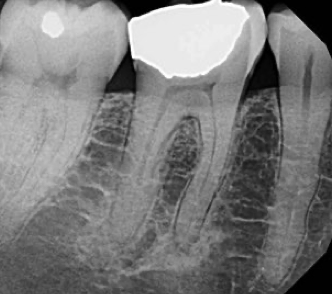

what radiographic analysis should be carried out during endodontic diagnosis?

A

• new periapicals (at least 2)

• bitewing

• cone beam-computed tomography